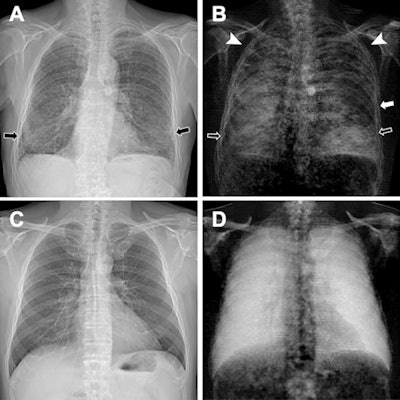

Figure 2: (A, C) Conventional attenuation-based chest x-rays and (B, D) dark-field chest x-rays in an 83-year-old man diagnosed with combined pulmonary fibrosis and emphysema (upper row) and a healthy 33-year-old man (lower row). Image courtesy of Radiology: Cardiothoracic Imaging.The patient (Fig 2: A, B) demonstrated substantially decreased dark-field signal in the upper lungs (left more than right), where emphysema is most severe, and inhomogeneous but decreased lower lung signal (due to presence of fibrosis) when compared with a healthy subject (Fig 2: C, D). The stronger manifestation of fibrosis in the right lower lobe compared with the left lower lobe, as was seen on CT images, corresponded well to the asymmetric reduction of dark-field signal in the lower fields with a right-sided predominance (Fig 2B), the authors wrote.

"As both fibrosis and emphysema lead to a reduction of dark-field signal -- due to a smaller number of intact alveoli -- the assignment of signal loss to one of the two pathologic conditions is hardly possible from the [dark-field chest x-ray] alone," the researchers wrote.

However, the combination of conventional and dark-field images might allow for the differentiation of emphysema and fibrosis, especially as the images are perfectly coregistered, they suggested.